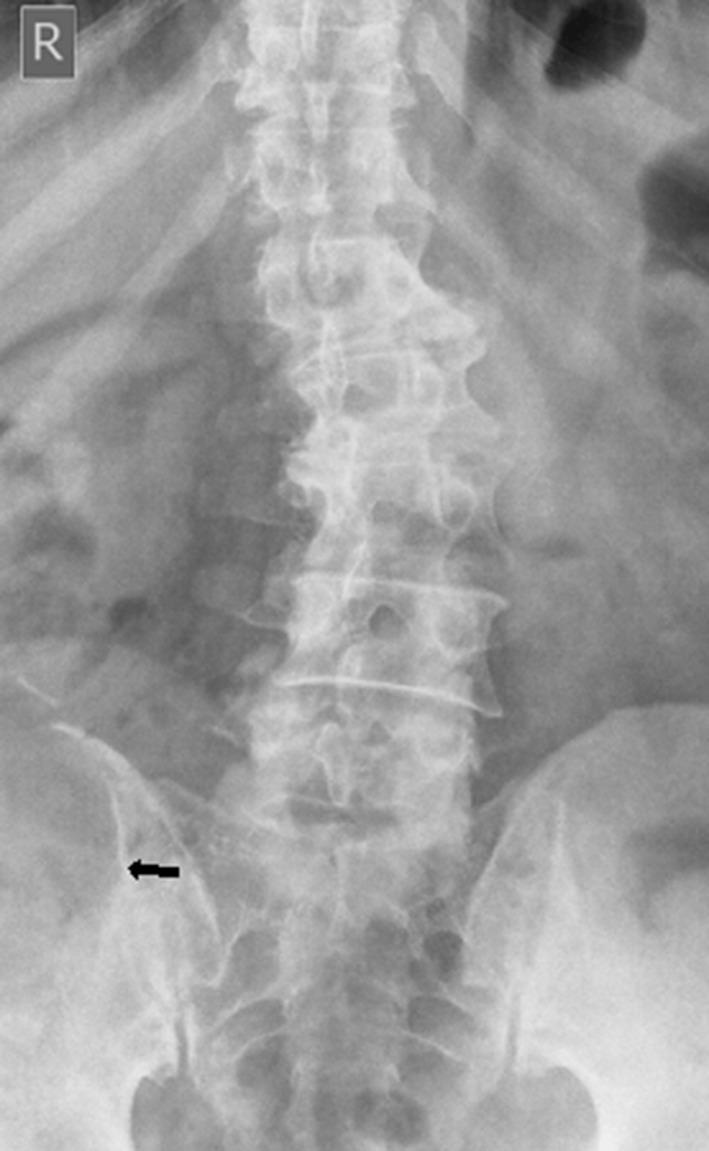

This report describes a huge chondromyxoid fibroma (CMF) that developed in the right iliac crest and wing. The tumour is rare, perhaps the rarest of all bone tumours, and its occurrence in the iliac crest and wing of a 63-year-old male is extraordinarily uncommon. The patient complained of gradual onset of right groin pain over a period of more than 2 years and low back pain and tender swelling of the right gluteal region over a period of another 1 year. Conventional radiography of the lumbar spine and pelvis revealed a large osteolytic lesion of the right iliac crest and wing associated with mild levoscoliosis. MRI of the pelvis revealed a huge well-defined lesion arising from the right iliac crest and wing and extending to the right paraspinal region, false pelvis and right gluteal region and displacing rather than invading the surrounding structures. The patient underwent surgery, and the mass was totally removed. The clinical manifestations, imaging findings and surgical treatment of the lesion are discussed.

本报告描述了一例发生于右髂嵴和髂骨翼的巨大软骨黏液样纤维瘤(CMF)。该肿瘤较为罕见,可能是所有骨肿瘤中最罕见的,其发生在一名63岁男性的髂嵴和髂骨翼极为少见。患者诉说在超过2年的时间里右腹股沟疼痛逐渐出现,在另外1年的时间里出现下背部疼痛以及右臀区域压痛性肿胀。腰椎和骨盆的传统X线摄影显示右髂嵴和髂骨翼有一个大的溶骨性病变,伴有轻度左旋脊柱侧弯。骨盆MRI显示一个巨大的边界清晰的病变,起源于右髂嵴和髂骨翼,延伸至右椎旁区域、假骨盆和右臀区域,推移而非侵犯周围结构。患者接受了手术,肿物被完全切除。本文讨论了该病变的临床表现、影像学表现及手术治疗。